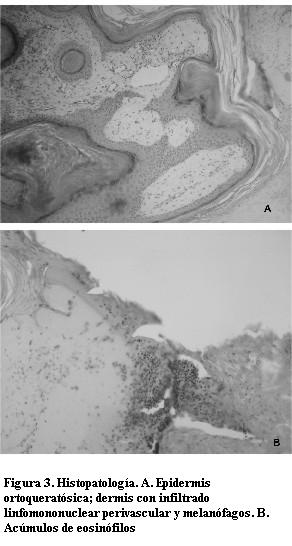

Se realiza diagnóstico clínico de incontinentia pigmenti; realizándose biopsia de piel de lesión hiperpigmentada (etapa 2–3) siendo compatible con éste. El estudio histopatológico informó las típicas alteraciones de esta enfermedad: epidermis ortoqueratósica, dermis con infiltrado linfomononuclear perivascular y melanófagos y acúmulos de eosinófilos (figura 3). Actualmente la paciente se encuentra bajo control y seguimiento de equipo multidisciplinario integrado por pediatra, dermatólogo pediatra, neuropediatra y odontólogo.

Otras de las características diagnósticas son la presencia de eosinofilia (1,2,15) y el estudio histológico de biopsia de piel que proporciona la confirmación diagnóstica (2).

Se observa acantosis, papilomatosis irregular e hiperqueratosis, con células disqueratóticas dispersas y remolinos escamosos, dilución de pigmento, alteraciones vacuolares y degeneración de la capa basal. El infiltrado inflamatorio leve con melanina dentro del melanófago en dermis papilar (“incontinentia pigmentaria”), se ve en la segunda y tercera etapa de la enfermedad.